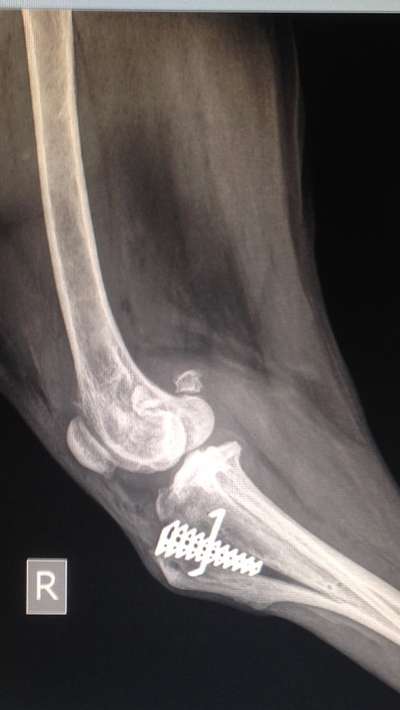

Hallo Tina🤗meine wilde Ronja hatte mit 10 Jahren ihre 1. Kreuzbandrissop-und voriges Jahr mit 12 Jahren am anderen Bein auch wieder eine Kreuzbandrissop. - sie hat beide gut überstanden‼️es wurde eine „ Spirale“ einoperiert, die die Bänder wieder zusammenhält(als Laie erklärt😃

Kreuzbandop